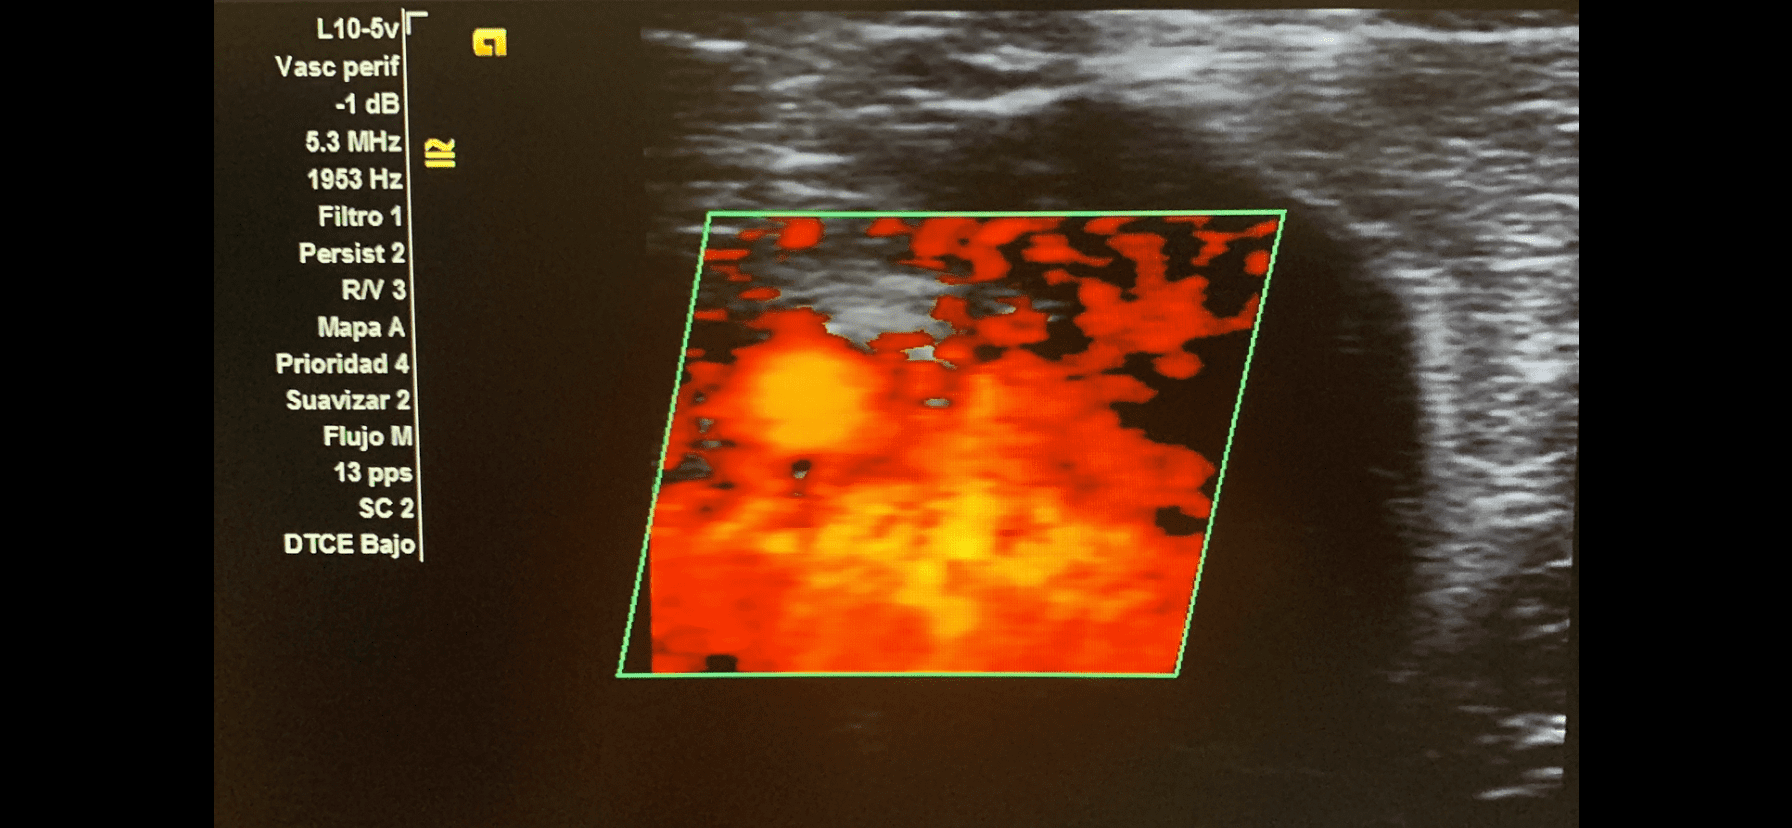

Imagen 1. Muslo derecho, lesión de bala.

Imagen 4. Flujo turbulento.